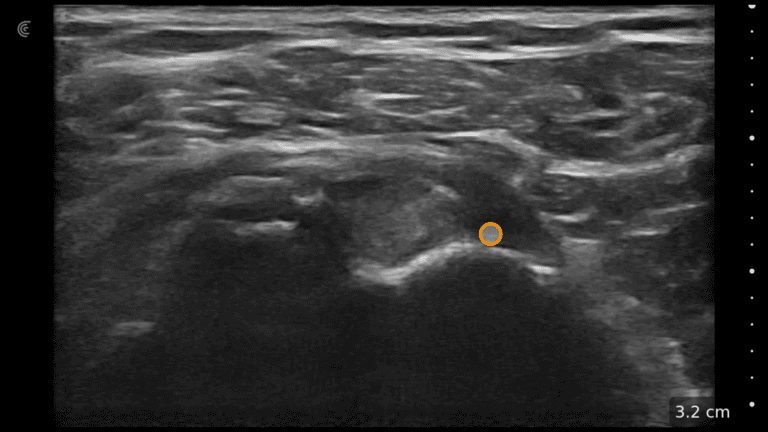

Dr. Ines Verner demonstrates how to visualize the facial, superior and inferior labial arteries. High-definition vascular imaging using Color Doppler allows her to visualize the locations and avoid intervascular injections.